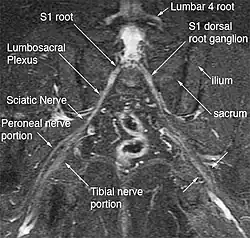

Magnetic resonance neurography (MRN) is the direct imaging of nerves in the body by optimizing selectivity for unique MRI water properties of nerves. It is a modification of magnetic resonance imaging. This technique yields a detailed image of a nerve from the resonance signal that arises from in the nerve itself rather than from surrounding tissues or from fat in the nerve lining. Because of the intraneural source of the image signal, the image provides a medically useful set of information about the internal state of the nerve such as the presence of irritation, nerve swelling (edema), compression, pinch or injury. Standard magnetic resonance images can show the outline of some nerves in portions of their courses but do not show the intrinsic signal from nerve water. Magnetic resonance neurography is used to evaluate major nerve compressions such as those affecting the sciatic nerve (e.g. piriformis syndrome), the brachial plexus nerves (e.g. thoracic outlet syndrome), the pudendal nerve, or virtually any named nerve in the body. A related technique for imaging neural tracts in the brain and spinal cord is called magnetic resonance tractography or diffusion tensor imaging.

The most significant impact of magnetic resonance neurography is on the evaluation of the large proximal nerve elements such as the brachial plexus (the nerves between the cervical spine and the underarm that innervate shoulder, arm and hand),[9] the lumbosacral plexus (nerves between the lumbosacral spine and legs), the sciatic nerve in the pelvis,[10] as well as other nerves such as the pudendal nerve[11] that follow deep or complex courses.

Neurography has also been helpful for improving image diagnosis in spine disorders. It can help identify which spinal nerve is actually irritated as a supplement to routine spinal MRI. Standard spinal MRI only demonstrates the anatomy and numerous disk bulges, bone spurs or stenoses that may or may not actually cause nerve impingement symptoms.[12][13]

Use of magnetic resonance neurography is increasing in neurology and neurosurgery as the implications of its value in diagnosing various causes of sciatica becomes more widespread.[25][26] There are 1.5 million lumbar MRI scans performed in the US each year for sciatica, leading to surgery for a herniated disk in about 300,000 patients per year. Of these, about 100,000 surgeries fail. Therefore, there is successful treatment for sciatica in just 200,000 and failure of diagnosis or treatment in up to 1.3 million annually in the US alone. The success rate of the paradigm of lumbar MRI and disk resection for treatment of sciatica is therefore about 15%(Filler 2005). Neurography has been applied increasingly to evaluate the distal nerve roots, lumbo-sacral plexus and proximal sciatic nerve in the pelvis and thigh to find other causes of sciatica. It is increasingly important for brachial plexus imaging and for the diagnosis of thoracic outlet syndrome.[27] Research and development in the clinical use of diagnostic neurography has taken place at Johns Hopkins, the Mayo Clinic, UCLA, UCSF, Harvard, the University of Washington in Seattle, University of London, and Oxford University (see references below) as well as through the Neurography Institute. Recent patent litigation concerning MR Neurography has led some unlicensed centers to discontinue offering the technique. Courses have been offered for radiologists at the annual meetings of the Radiological Society of North America (RSNA), and at the International Society for Magnetic Resonance in Medicine and for surgeons at the annual meetings of the American Association of Neurological Surgeons and the Congress of Neurological Surgeons. The use of imaging for diagnosis of nerve disorders represents a change from the way most physicians were trained to practice over the past several decades, as older routine tests fail to identify the diagnosis for nerve related disorders. The New England Journal of Medicine in July 2009 published a report on whole body neurography using a diffusion based neurography technique.[28] In 2010, RadioGraphics - a publication of the Radiological Society of North America that serves to provide continuing medical education to radiologists - published an article series taking the position that Neurography has an important role in the evaluation of entrapment neuropathies.[29]